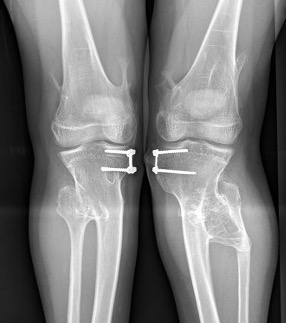

Knee - genu valgum

Genu Valgum OCMultiiple OCMultiple OC

Knee

Knee valgus OCOsteochondroma Knee Lateral

Incidence

Clement et al Knee 2014

- 172 patients with HME

- 90% had exostosis around the knee

- 20% had valgus deformity

- 15% had FFD deformity

Guided growth / temporary hemi-epiphysiodesis

Guided growth

Guided growth valgus HMEGuided growth 2 HME